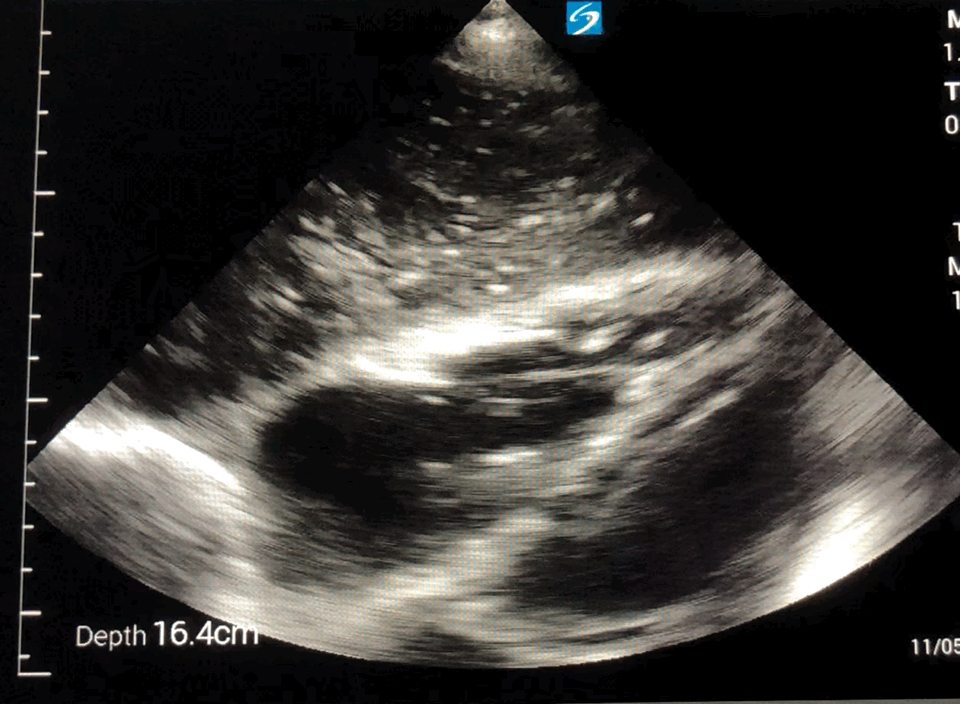

SC view

SC view with cardiac standstill: complete cardiac standstill is observed. No movement is seen in the heart musculature or valves, indicating the absence of cardiac activity. This finding is consistent with cardiac arrest and signals a poor prognosis unless reversible causes are quickly identified and addressed.